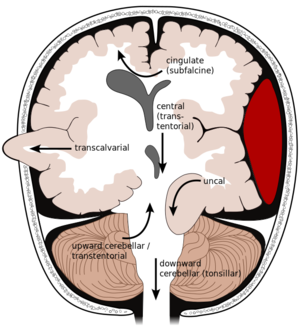

أنواع نزيف المخ